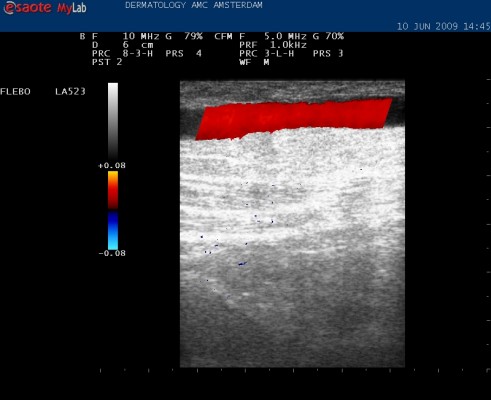

A leaky barrel in the depths: colored red on the Duplex screen |

On the Duplex device's screen, the vessels are visible as black indentations against a grayish-white background. If your calf is squeezed during the examination, the blood will flow upward. This is indicated by a blue color on the screen – this is normal. If the valves are not functioning properly, the blood will flow back down the varicose vein. This is indicated by a red color on the screen – this means the valves are not functioning properly. By examining various areas – the groin folds, the backs of the knees, and elsewhere on your leg – a clear picture of the leak and what needs to be treated

is obtained. You will then receive advice and treatment plans. You will also receive written information to read at home.HOW IS THE BEST TREATMENT DETERMINED?This is determined based on the findings during the examination. If you only have small varicose veins on the outside of your leg, injection ( sclerosis ) is the best solution. If there are very small ones, so small that a needle cannot fit, they can be treated with an external laser treatment. For medium-sized varicose veins, sclerotherapy is also the best solution. For very large varicose veins, sclerotherapy is not the best treatment because it often becomes ineffective: the vessel can reopen later. Furthermore, a large amount of sclerosant must be injected. These varicose veins are best cauterized from within ( endovenous treatment with the VNUS method ). Alternatively, foam sclerotherapy can be used. For very tortuous varicose veins or large varicose veins that lie just beneath the skin, cauterization from within is not effective. In that case, the vascular surgeon can surgically remove (strip) the vessels. The vascular surgeon can also connect the connections to the deep system (perforantectomy). Large side branches of the main veins are best removed through small incisions under local anesthesia. This is called the Muller procedure (outpatient phlebectomy). If the valves in the vessels of the deep system are defective, then treating external varicose veins is not very effective. In that case, you should wear elastic stockings (compression therapy).OVERVIEW OF THE DIFFERENT TREATMENTS FOR VARICOSE VEINSElastic stockings and pressure bandages (compression therapy) Sometimes it is decided not to treat varicose veins. For example, because the deep vein system is compromised. Or because treatment is not yet possible, for example, during pregnancy or shortly after a deep vein thrombosis. In these cases, wearing elastic stockings can significantly reduce symptoms.